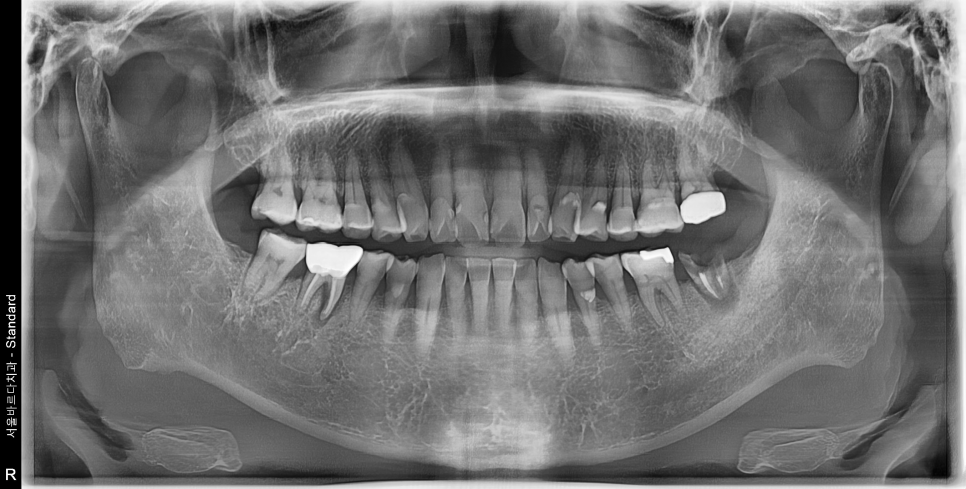

먼저 치과치료의 가장 기본에 해당하는 X-ray들을 보겠습니다.

어금니에 잇몸이 안좋아보이는 부분들이 몇군데 보이는군요.

자세히 보는 작은 X-ray를 추가로 촬영합니다.

흠.. 생각보다 더 많이 심각한 상태입니다.

특히나 뿌리만 남은 치아는 내부에 골소실이 심각한 상태입니다.